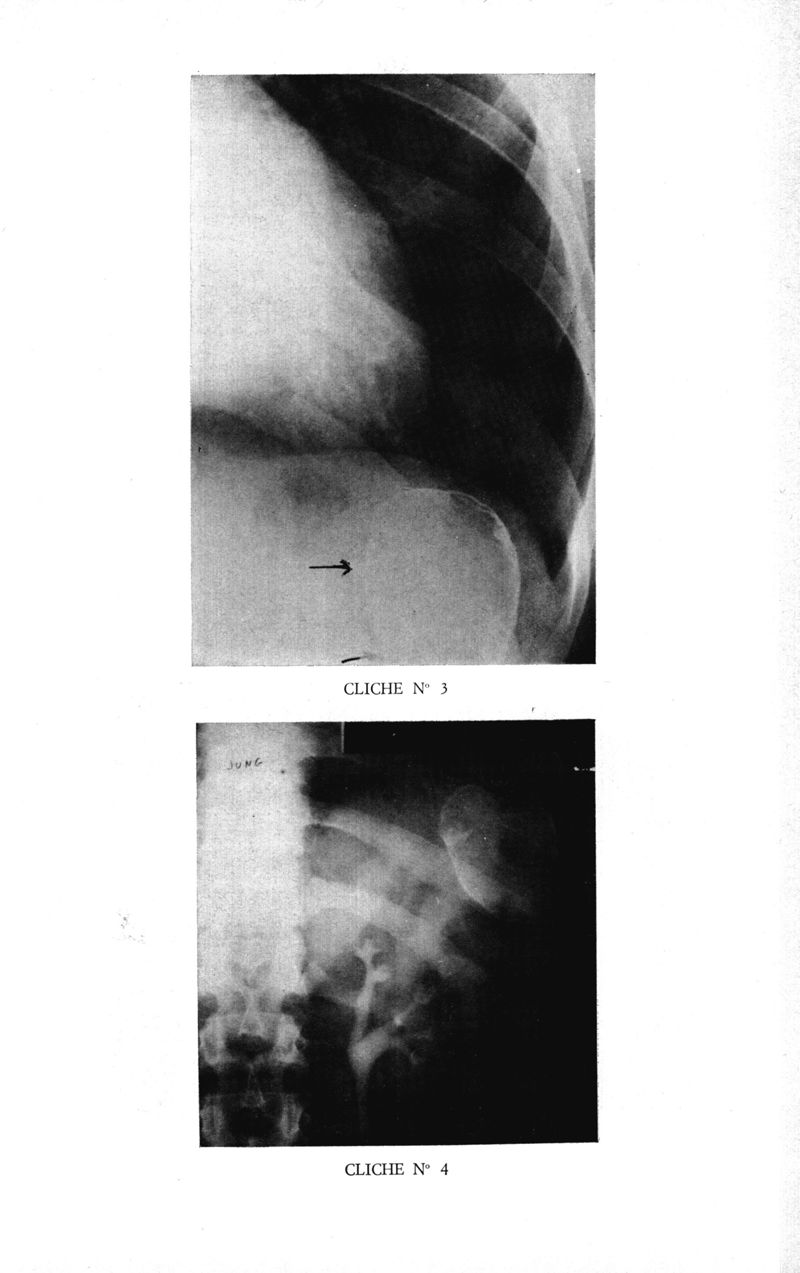

Médecine tropicale: revue française de pathologie et de santé publique tropicales

. - Marseille, 1974.